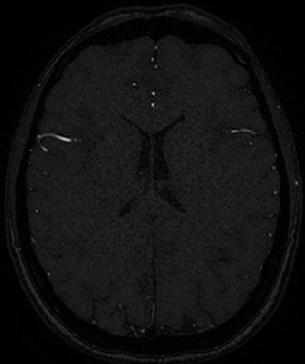

4.4 Qualitative Results

We show sample visual results of representative slices in Figure 3. Sample 3D visual results are given as surface renderings of segmentation maps in Figure 4.

| Baseline GAN | sGAN | Ground Truth | |

|---|---|---|---|

![]() |

|